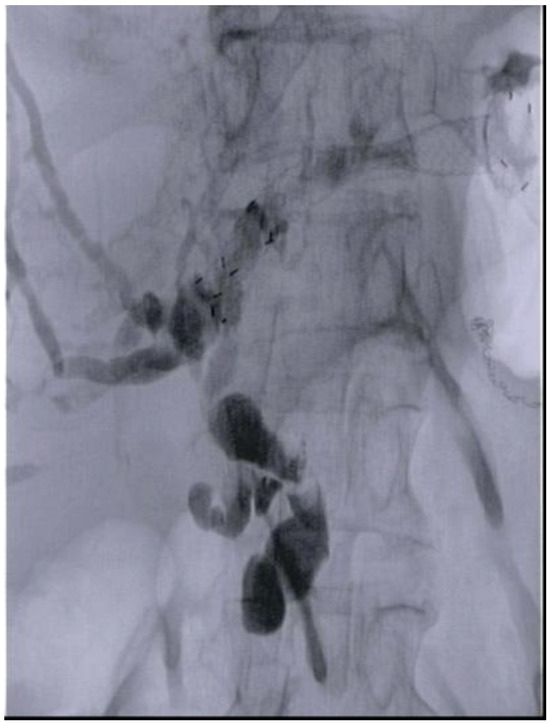

5. EUS Hepaticogastrostomy